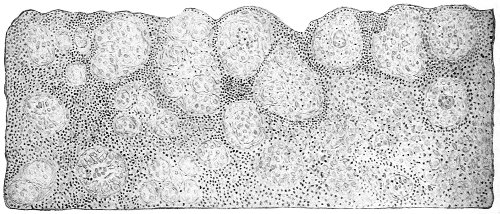

Several varieties of acute vaginitis may be recognized—the simple, the granular, the senile, and the emphysematous. It is unusual to find the entire surface of the vagina involved. The disease is confined to areas or patches separated by healthy tissue.

In simple vaginitis the inflamed membrane remains smooth.

In granular vaginitis, which is the variety usually seen, the papillæ are infiltrated with small cells, and are much enlarged, so that the inflamed surface has a granular appearance.

Senile vaginitis is due to infection of portions of the vaginal mucous membrane that have lost their epithelium as a result of the atrophic changes of old age. This disease occurs in patches of various size, sometimes presenting the character of ecchymosis; in other cases the 50 patches have altogether lost the epithelium, and permanent adhesions may take place between areas which are brought in contact. This form of vaginitis has also been called adhesive vaginitis. It is said that a similar condition may occur in children.

The emphysematous form of vaginitis occurs in pregnancy. The vaginal walls are swollen and crepitating. The gas is contained in the meshes of the connective tissue.